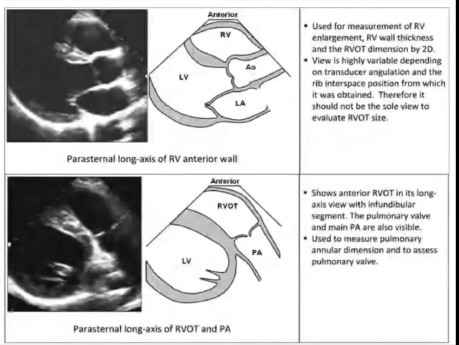

Echokardiograficzna ocena ilościowa prawego serca

Echokardiograficzna ocena ilościowa prawego serca. Prelegent: Dr Shamon Ahmed. Cele: 1. Przejrzyj aktualne wytyczne dotyczące ilościowej oceny/pomiarów prawej części serca. 2. Omów ograniczenia związane...